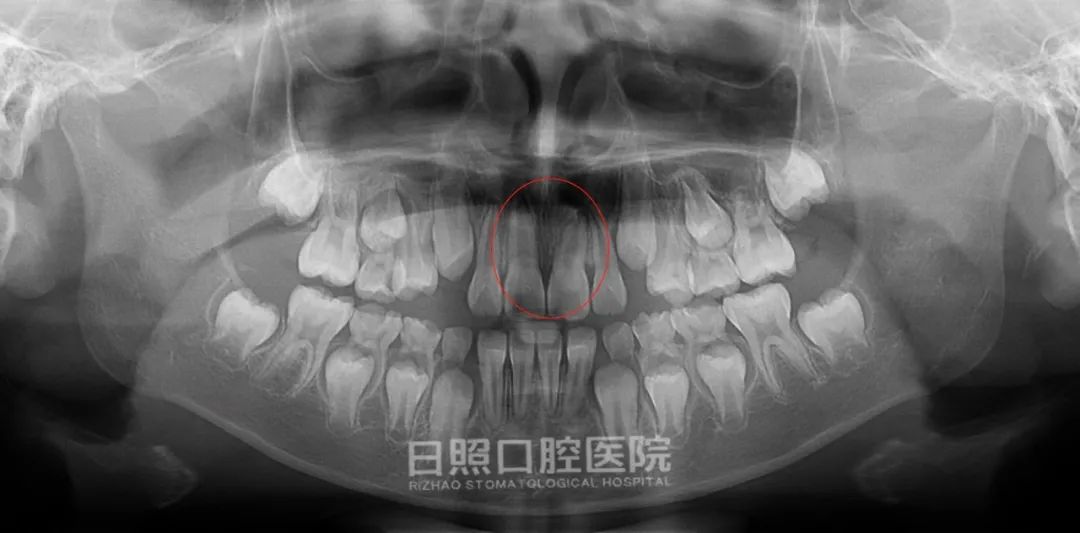

矫治过程结束了,再拍一张全景牙片看一下吧,倒置埋伏阻生牙“迷途知返”,乖乖地呆在了正确的位置。